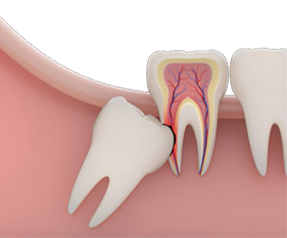

GÖMÜK DİŞLER

DETAYLI BİLGİ